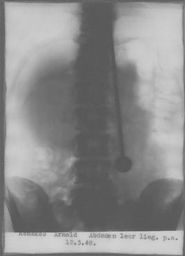

Dans ce reportage d'époque, on peut voir qu'il passe des tests dans une clinique avec radiographies

Les médecins ne découvrent aucune supercherie, les armes traversent bel et bien son corps